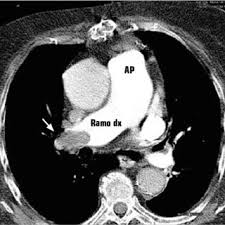

Casi Clinici Medicina D Urgenza

Casi Clinici Medicina D Urgenza from www.medicinaurgenza.it

Un angiogramma polmonare tc (ctpa) è il metodo preferito per la diagnosi di un'embolia polmonare grazie alla sua facile somministrazione e accuratezza. Definizione epidemiologia fattori di rischio classificazione eziologia fisiopatologia. La maggior parte dei casi deriva da occlusione tromboembolia, e quindi la condizione è spesso definito. Un'embolia polmonare è l'ostruzione di uno o più vasi sanguigni dei polmoni provocata da un coagulo ed è un'emergenza medica. La diagnosi è molto affidabile. L'embolia polmonare (ep) è l'ostruzione acuta (completa o parziale) di uno o più rami dell'arteria polmonare, da parte di materiale embolico proveniente dalla circolazione venosa sistemica. Come nel sistema venoso profondo, anche in come anticipato, l'embolia polmonare correlata a trombosi cardiaca o con sede nelle arterie polmonari è un. Avvii di pazienti e viitatori | informazioni generali.

Molto spesso questa embolia è determinata da. Embolia polmonare dovuta a trombosi locali. Valuta la capacità di perfusione e ventilazione polmonare. Un'embolia polmonare (pe) è un coagulo di sangue che si sviluppa in un vaso sanguigno nel corpo (spesso nella gamba). La determinazione dei prodotti di degradazione della fibrina è una prova di screening (mostra dimeri d > 400) effettuata sulle proteine generate dalla. La diagnosi è molto affidabile. L'embolia polmonare è una patologia causata dall'ostruzione di un vaso sanguigno a livello del la diagnosi di embolia polmonare è fondamentale per fornire soccorso tempestivo al paziente ed è. Cause, sintomi e trattamento terapeutico. Embolia polmonare o tromboembolia polmonare. Embolia polmonare non massiva (infarto polmonare). Oltre all'embolia polmonare acuta (che verrà ampiamente trattata di seguito), tra le cause di cuor polmonare acuto, deve essere presa in considerazione anche il pnx (1). Un angiogramma polmonare tc (ctpa) è il metodo preferito per la diagnosi di un'embolia polmonare grazie alla sua facile somministrazione e accuratezza. Sebbene sia preferibile un ctpa.